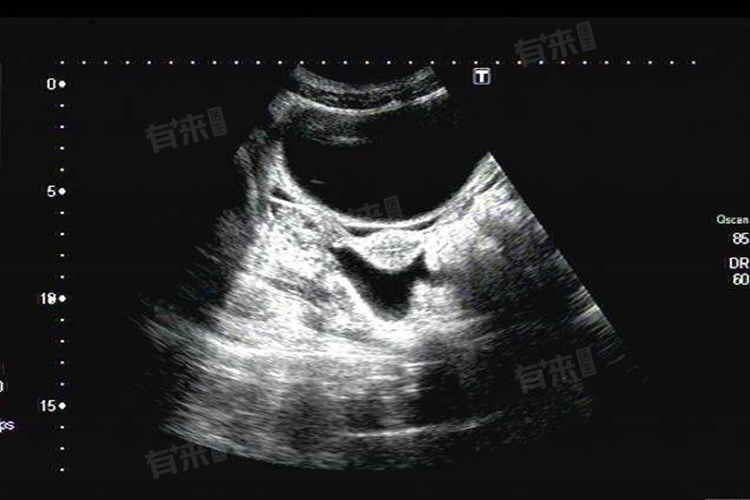

孕早期盆腔积液是指在妊娠初期,通过超声检查发现盆腔内存在液体聚集的现象,可能由多种因素引起,如激素水平变化、胚胎着床、炎症感染等。

4、异位妊娠:受精卵着床于子宫以外的部位,如输卵管、卵巢等,称为异位妊娠。当异位妊娠破裂或流产时,可引起盆腔内出血,表现为盆腔积液。此类情况属急腹症范畴,需紧急处理,以保障孕妇生命安全。